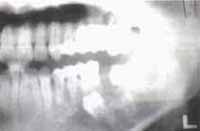

CASO 2

Fig. 13A. En la proyección lateral oblicua se observa un gran quiste dentígero que contiene en su interior el segundo molar inferior izquierdo. Puede notarse además el desplazamiénto del tercer molar por la presión del quiste y la importante reabsorción radicular del primer molar.

Fig. 14A – Fig. 14B Radiografía panorámica de control un año después de realizada la Marsupialización (Fig. 14A) mostrando la disminución del tamaño de la lesión además de los molares hacia su ubicación anatómica. La Fig. 14B corresponde a una etapa más avanzada del proceso de neoformación ósea y migración dentaria (Control radiográfico a dos años) que sugieren la proximidad del procedimiento quirúrgico definitivo.

Fig. 15 Radiografía panorámica realizada a los dos años y tres meses, inmediata a la exodoncia y toma de biopsia de tejido óseo y membrana quística residual para estudio histopatológico.